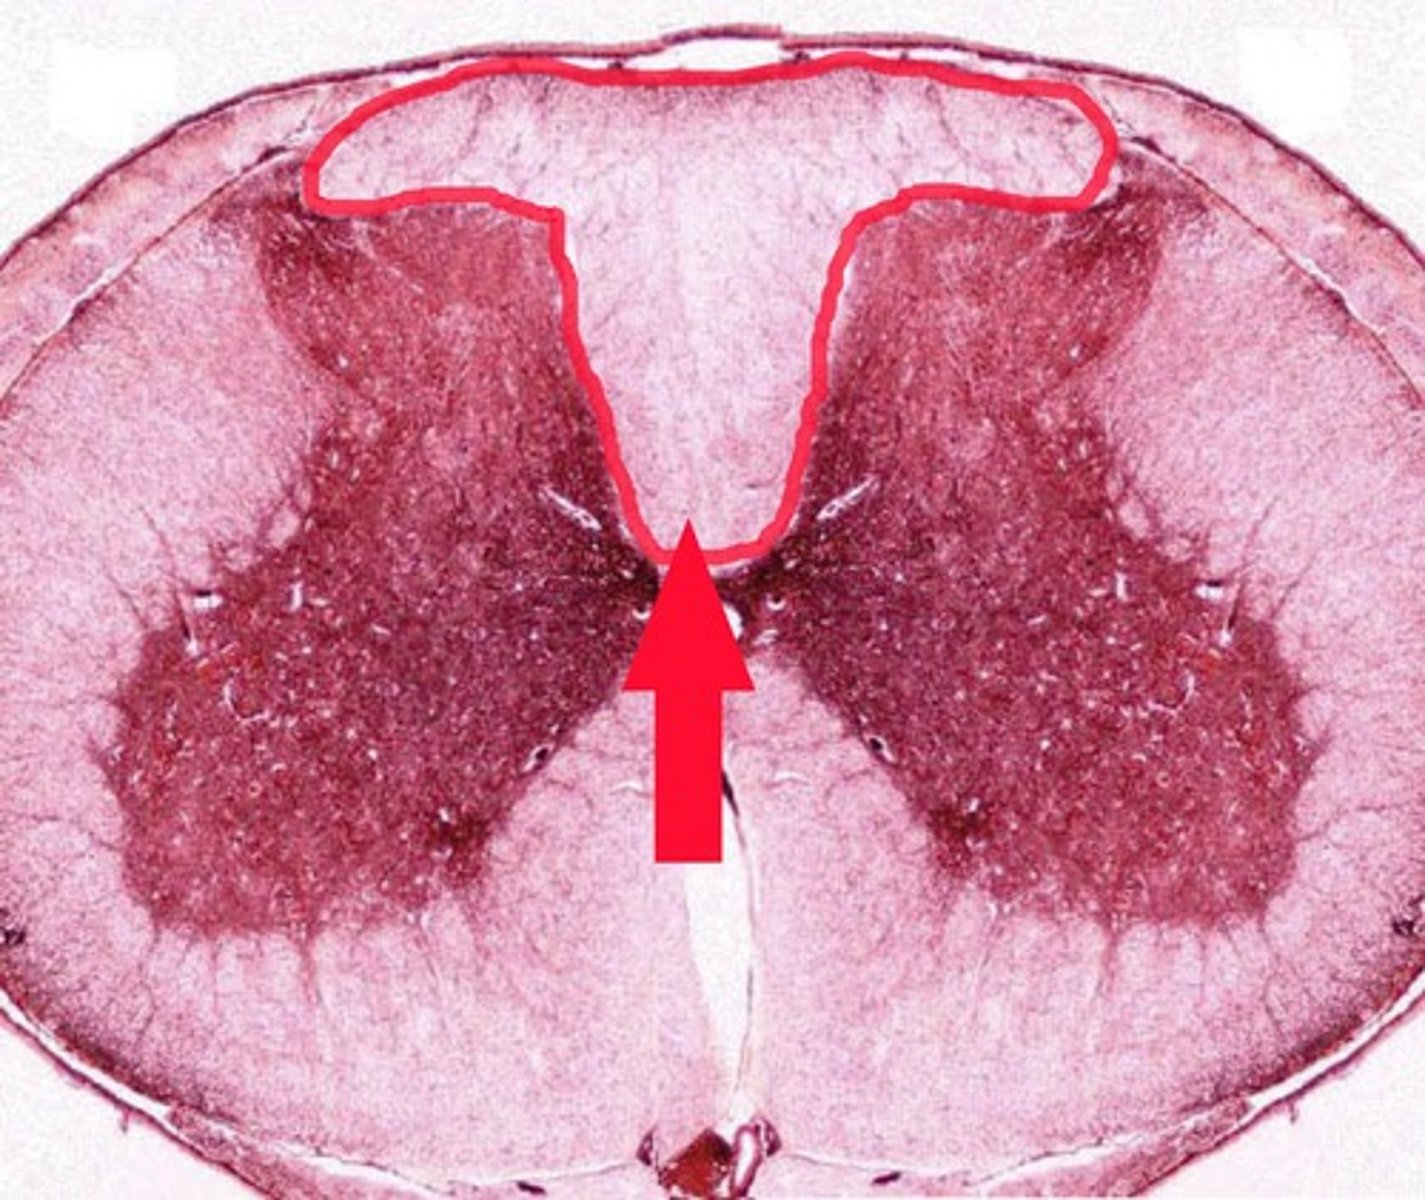

Gray Matter

1

Posterior Horn

2

Anterior Horn

3

Lateral Horn

4

Gray Commissure

6

Central Canal

5

White Matter

7

Posterior funiculus

8

Anterior Funiculus

9

Lateral Funiculus

10

Anterior Median Fissure

B